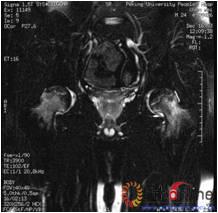

图3-1 女,31岁,SARS患者骨坏死,(1)MRI示双侧股骨头坏死,右Ⅱb(B型),左Ⅱc(C1型);(2)打压植骨术(未加BMP2)后坏死修复不完全,仍遗留股骨头软骨下病灶未完全修复, 5年随访关节功能优(Harris评分96分)